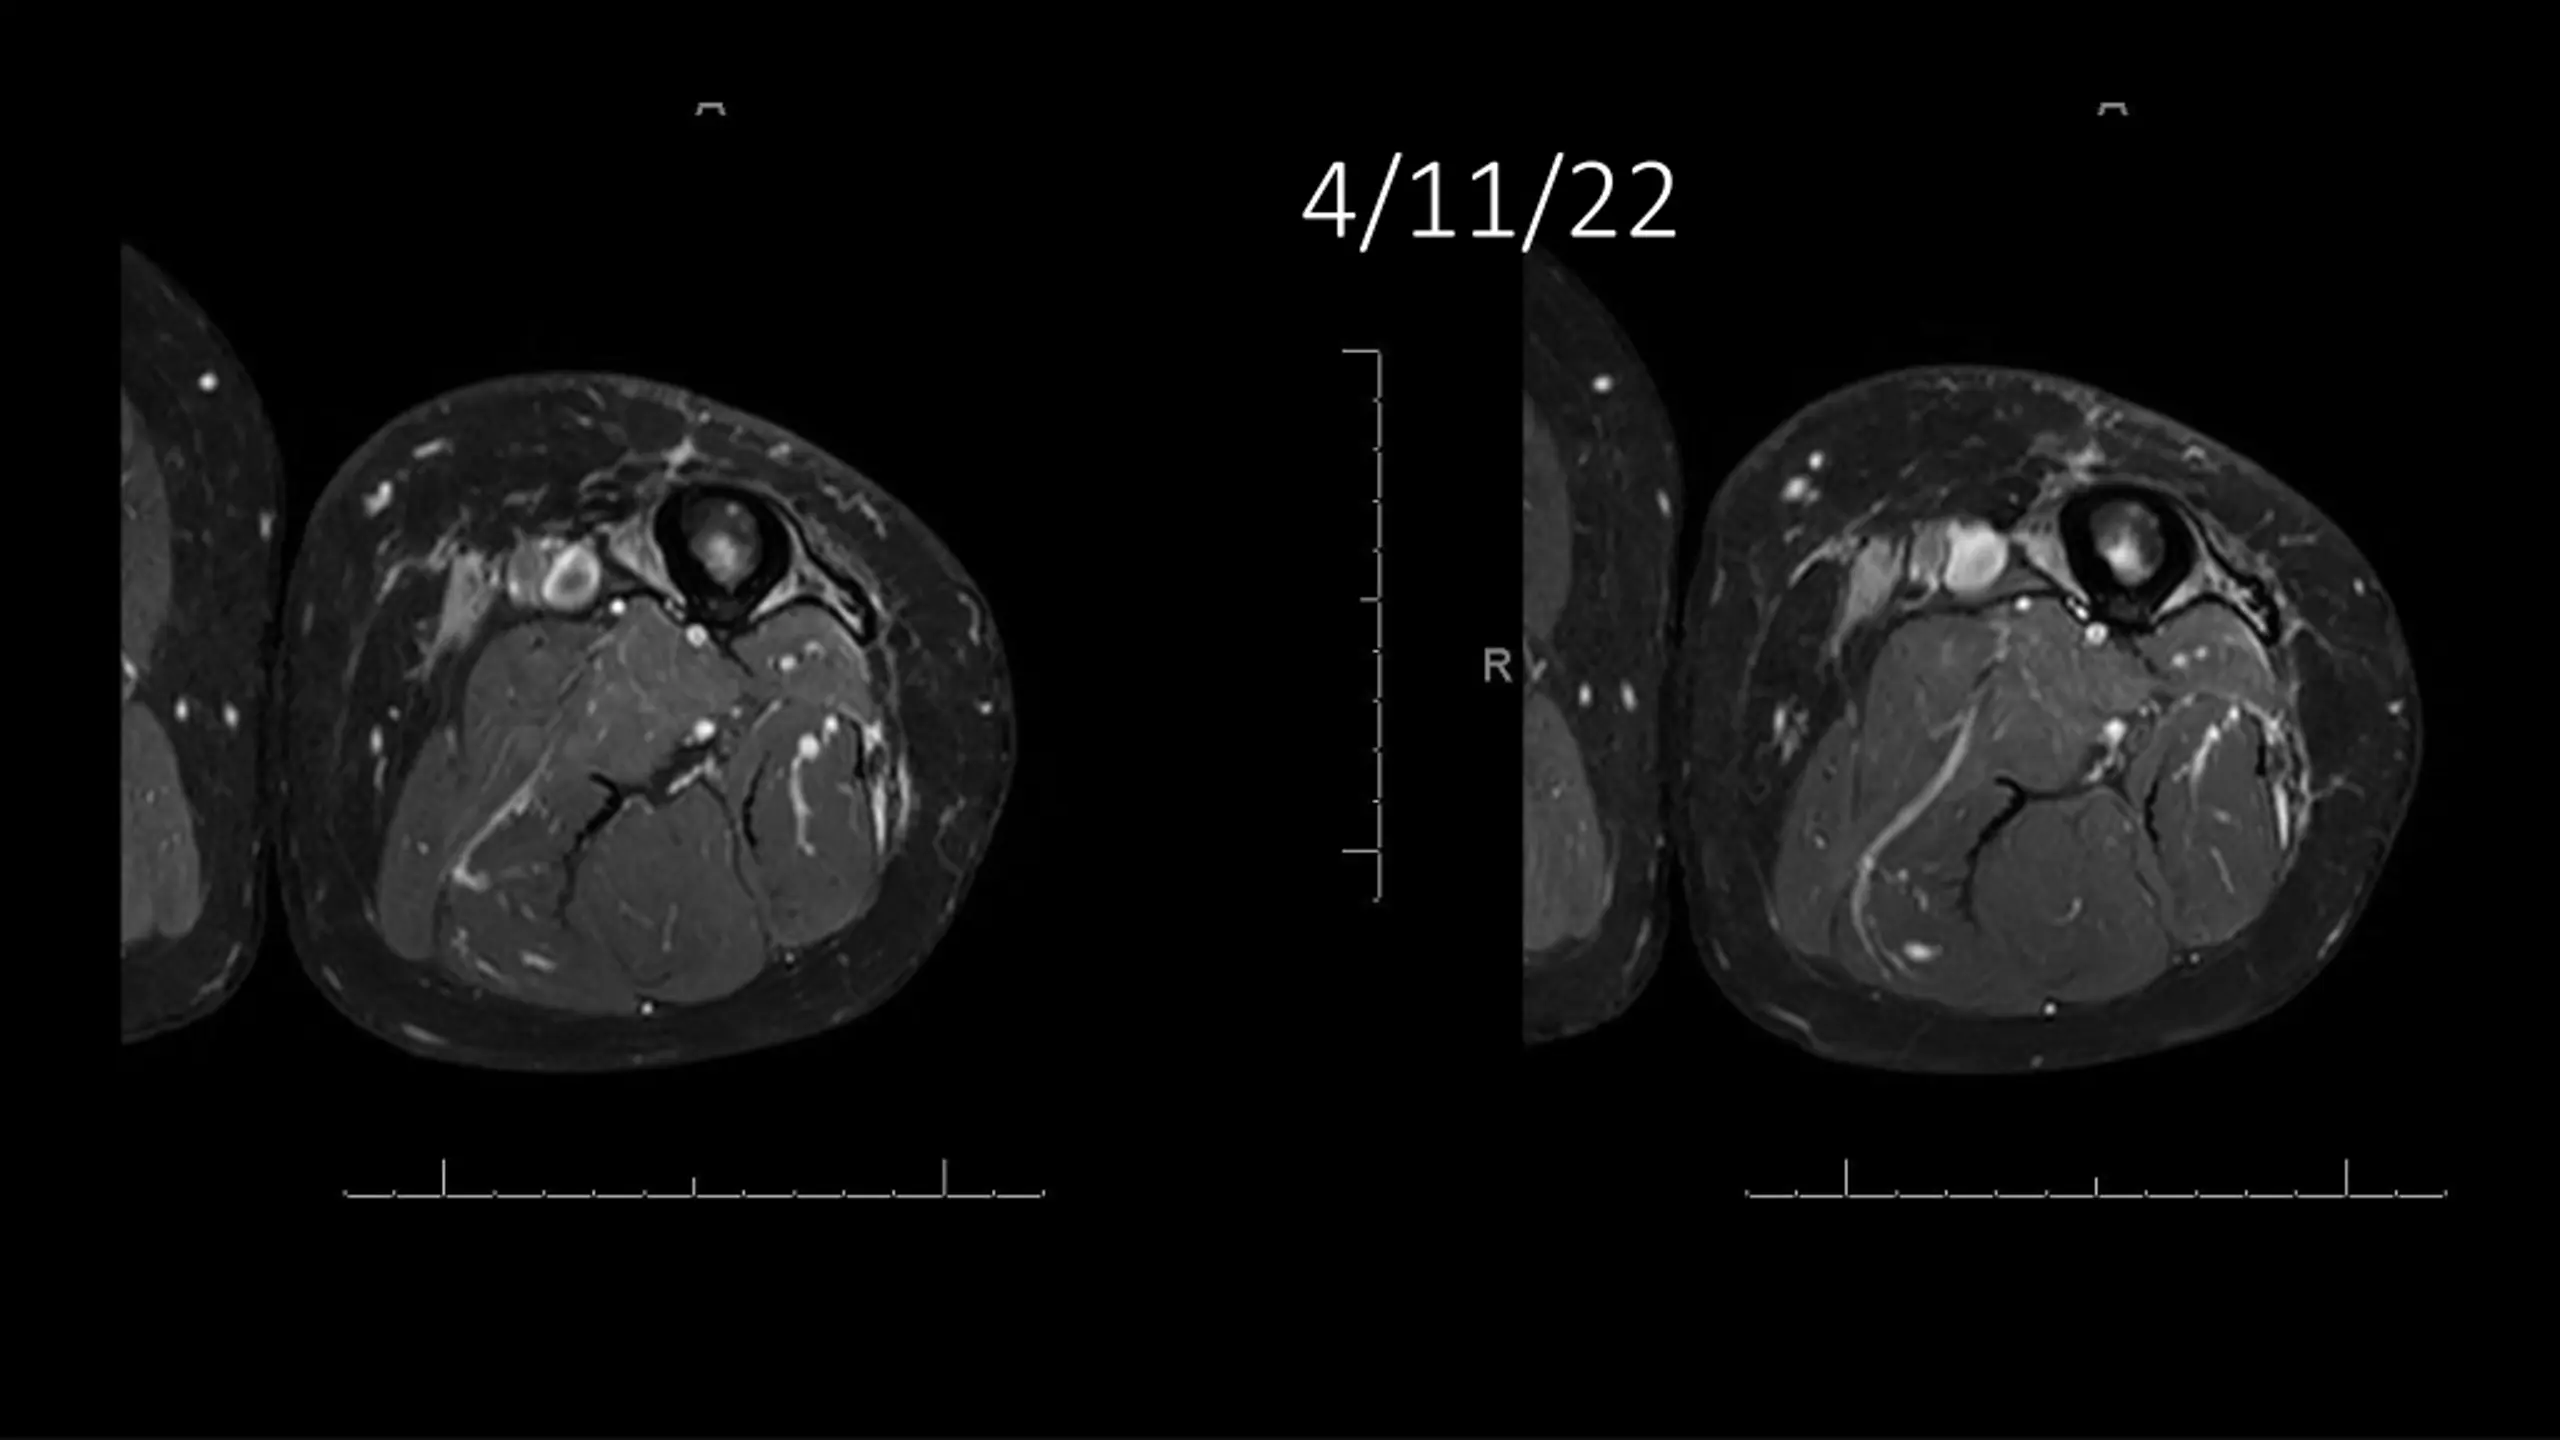

62-year-old shows post-surgery progress from 11/4/2020 to 4/11/22

Explore the journey of a 62-year-old individual post-UPS resection on 11/4/2020, through a series of dated images leading up to 4/11/22. Witness the transformation and recovery process in these visual updates reflecting the progression over time.